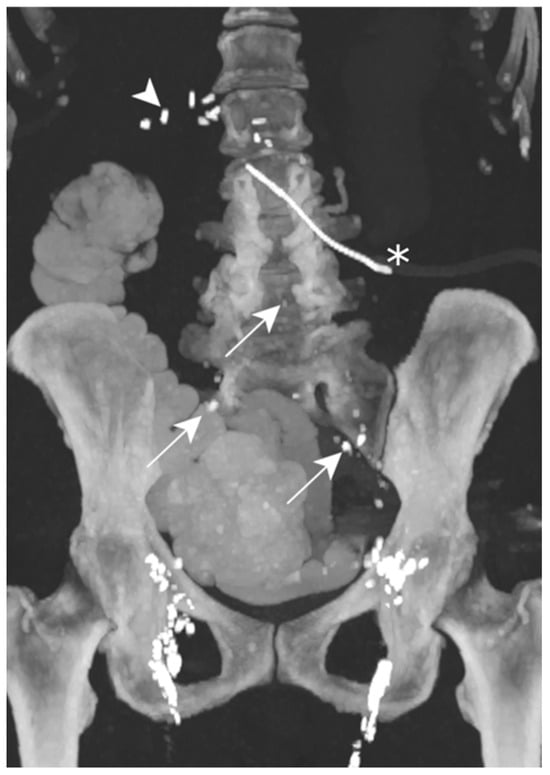

The contrast injected in the inguinal region showed ascension into the thoracic duct up to the level of the inferior vertebral plateau of D7, as well as the leakage and accumulation of Lipiodol in both pleural spaces: Lipiodol also accumulated in the drain coming into contact with the esophago-jejunal anastomosis (Figure 5).

Figure 5.

Patient A. The maximal-intensity projection of the CT scan reconstructed in the coronal plane. The Lipiodol injection shows opacification of the left inguinal and prevertebral lymphatic chains up to the level of the inferior vertebral plateau of D7 (white arrow). The drainage of the contrast agent through the catheter along the oesophagojejunal anastomosis is highlighted (white arrowheads). The subtle soft attenuation in the projection of the left lung field (white circle) corresponds to the accumulation of contrast in the pleural space due to the lymphatic rupture. The bilateral pleural catheter (white asterisks) and peritoneal drain (black asterisk) are identified.

One day after lymphangiography, the drain output had diminished by half, and reduced to less than 100 mL/d as of day 2. Per-mouth nutrition was begun progressively, with no recurrence of chylous effusion, allowing for drain removal on day 13.

Lymphangiography was therefore successful in treating this bilateral post-operative chylothorax.